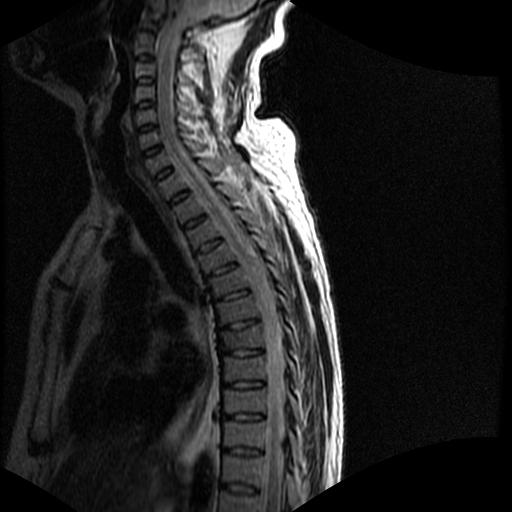

标题: MRI0985:胸椎.68岁男性,胸部疼痛,

68岁男性,胸部疼痛,不适。

t7椎体前1/3信号略减低,椎体上下面凹陷,相应脊髓几周边软组织信号未见改变。考虑:椎体退变。

胸7椎体楔状变形及信号异常,附件未见明显异常信号.椎间隙正常.未见软组织块影.考虑骨质疏松所致压缩性骨折可能大.

胸7椎体楔状变形及信号异常[t1t2 均为低信号],附件未见明显异常信号.椎间隙正常.未见软组织块影.考虑陈旧性压缩性骨折伴退变。